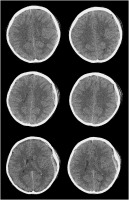

Kontusionsblutung

Abbildung 3: Verlauf einer Kontusionsblutung akut, 24 und 72 Stunden nach Trauma